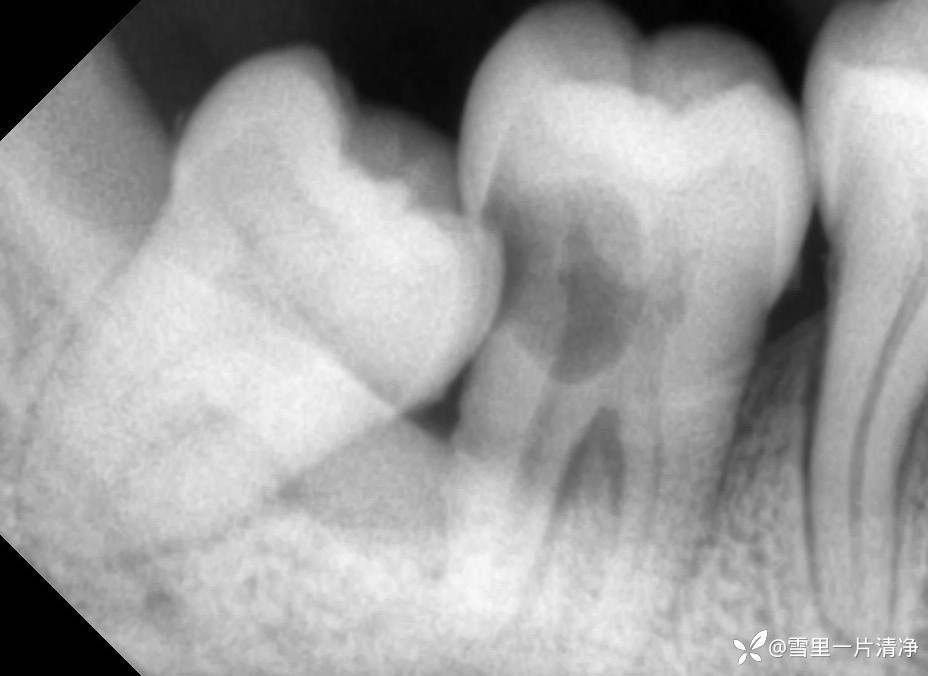

第二磨牙:治疗建议

8号牙在作祟:

7号牙2度松动,牙内吸收波及根干

正常来说7、8一起拔,种7,是最win的方案

其次摆烂方案是直接拔除第二磨牙,保留8